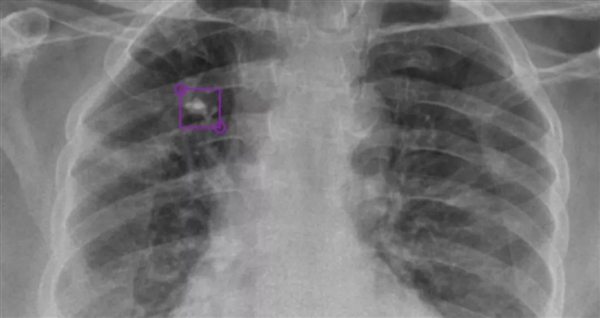

DeepTek AI模型檢測到的右上葉肺部鈣化結(jié)節(jié)

DeepTek希望通過AI驅(qū)動的放射平臺,大大提升全球在醫(yī)學影像診斷領(lǐng)域的能力,為此開發(fā)了全新的DxTB工具,用來篩查肺結(jié)核的X射線圖像,并標記病例,以供醫(yī)學專家進行優(yōu)先檢查。